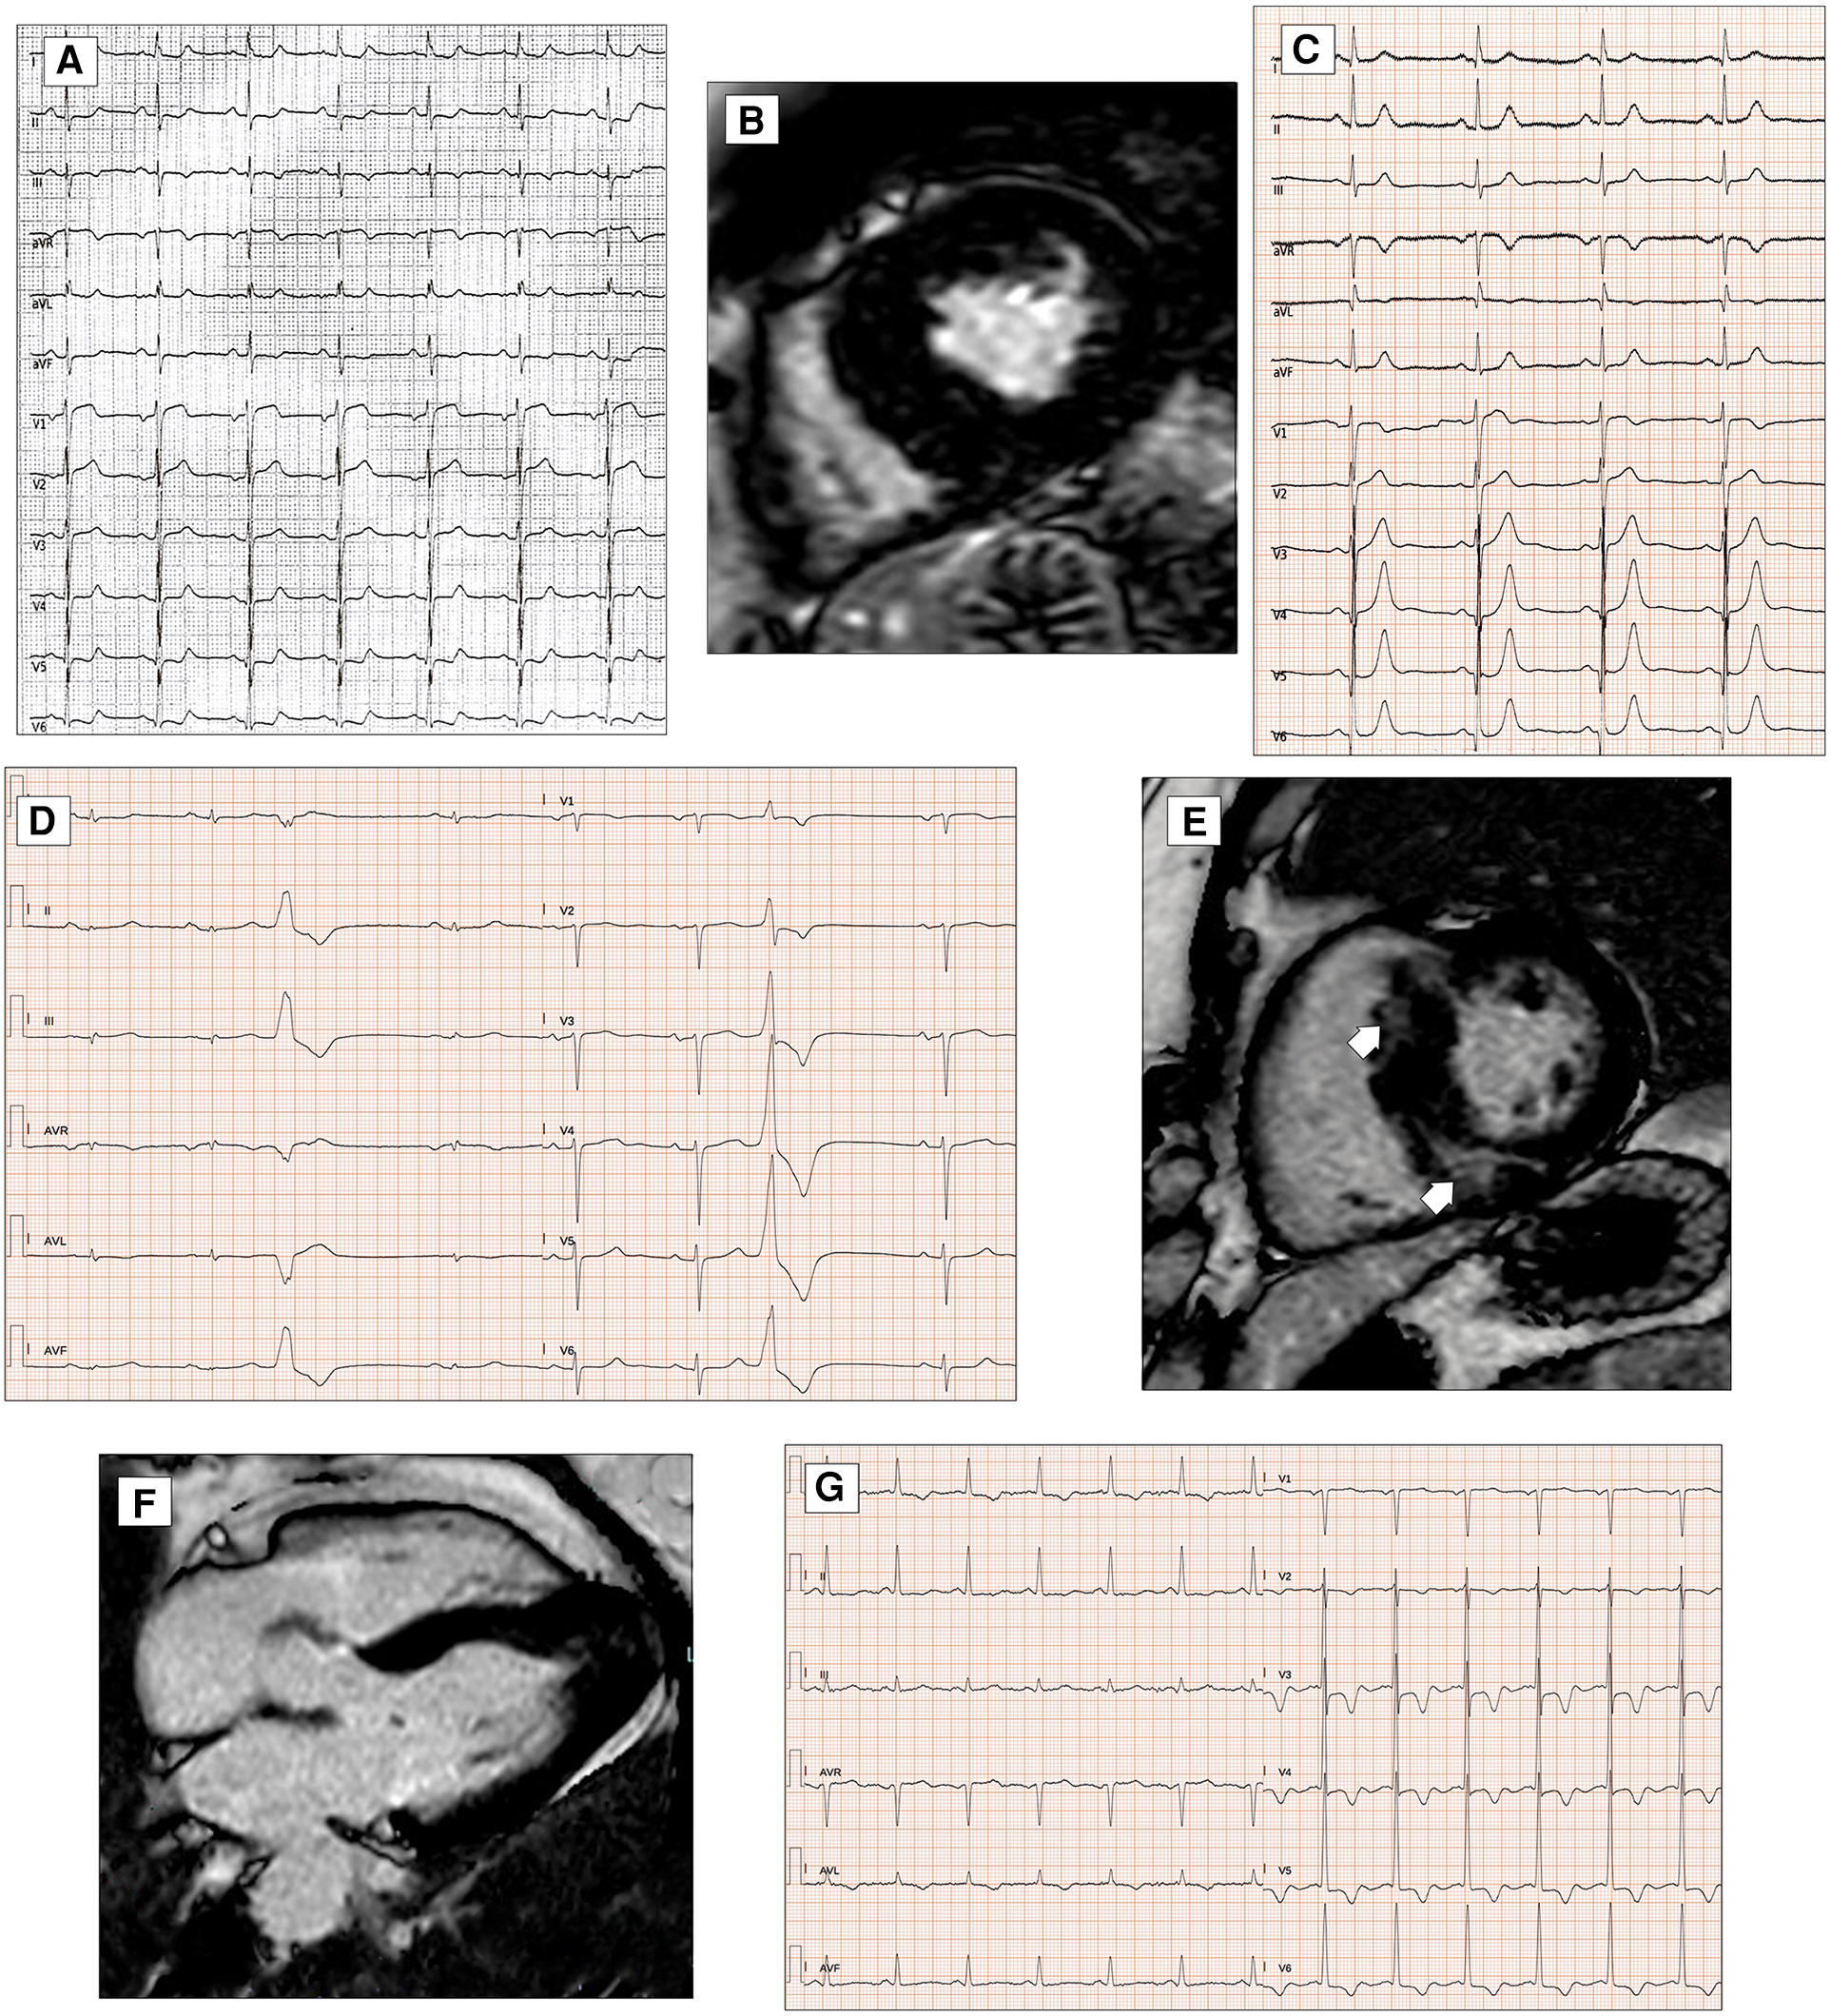

Figure 5

ECG abnormalities in patients with hypertrophic cardiomyopathy. ECG and CMR findings in a 78-year-old patient with obstructive HCM. Twelve-lead ECG showing ST-segment alterations in infero-lateral leads (A). Post-contrast CMR images in short axis showing hypertrophic septal asymmetric cardiomyopathy (B). Pathological Q waves in lateral leads and signs of LVH (Sokolow–Lyon criteria) in a 55-year-old male with non-obstructive HCM (C). ECG and CMR findings in a 56-year-old male with non-obstructive HCM. Note the low QRS voltages in limb leads at 12-lead ECG (D). LGE is found at the insertion points of the interventricular septum with hazy mid-wall enhancement in areas of hypertrophy (white arrows, E). CMR and ECG findings in a case of apical HCM in a 56-year-old female. CMR reveals obliteration of the cavity at the apex and the apical displacement of papillary muscles (F). ECG shows signs of LVH and deeply inverted T waves in precordial leads and lateral leads (G). All the ECGs presented in the figure were performed at 25 mm/s with 1 mm/mV. ECG, electrocardiogram; CMR, cardiac magnetic resonance; HCM, hypertrophic Cardiomyopathy; LGE, late gadolinium enhancement; LVH, left ventricular hypertrophy.

The QRS complex in patients with HCM is often abnormal. The classic signs of left ventricular hypertrophy, such as the Sokolow–Lyon and Cornell signs (SV3 + RaVL with a cutoff for LHV of >2.0 mV in women and >2.8 mV in men), are present in isolation in almost 2% of the patients (Figure 5C), contrary to what one might think (92). A small observational study showed that all ECG voltage criteria had a poor correlation with left ventricular mass and maximal thickness measured by MRI (93). Conversely, in patients with HCM, high-voltage QRS complexes are often accompanied by other pathological morphologies of the QRS complex and the ST-T tract.

A recent study published by Pelliccia et al. (94) demonstrated that low QRS voltages are present in 11% of patients with HCM and are associated with a larger extent of LGE on MRI (Figure 5D,E); furthermore, after a follow-up of 4.5 ± 2.6 years, the presence of LQRSV in HCM are associated with a higher incidence of functional deterioration, stroke, and ICD implant.

The presence of an fQRS complex has been correlated with the presence of myocardial fibrosis detectable on MRI (95). In 2015, a study by Konno et al. (96) demonstrated how the number of leads that showed the presence of a fQRS was the best predictor of the evidence of LGE on MRI.

Pathological Q waves are present in almost 40% of patients with HCM (Figure 5C). This could be another electrocardiographic expression of the presence of myocardial fibrosis or, as some have suggested, could also be due to abnormal activation of the septal or free wall portion at the level of the base of the left ventricle (83). The evidence of LGE on MRI was alternatively correlated with the ECG finding of Q waves in patients with HCM. The presence of LGE on MRI and evidence of Q waves on ECG have shown varying degrees of correlation over the years (97). In 2007, Papavassiliu et al. (98) hypothesized that not so much the presence of LGE but the distribution and, in particular, the segmentarity, the transmurality, and also the ratio of the thickness of the interventricular septum and posterior wall assessed on MRI were the real determinants of the presence or absence of Q waves on ECG. Chen et al. (99) demonstrated that the presence of pathological Q waves in lead D III, in the context of other signs of left ventricular hypertrophy, may distinguish patients with HCM from athletes, regardless of other ECG markers.

Not particularly useful for diagnostic purposes due to low sensitivity and specificity, predominantly left intraventricular conduction delays are considerably more frequent in the postoperative phase after myectomy or alcohol ablation of the septum, used for resolving the gradient at the ventricular outflow in obstructive forms and advanced disease (83). On the other hand, repolarization abnormalities are very common, primarily ST strain, defined as ≥1 mm concave downsloping ST-segment depression with asymmetrical T-wave inversion in the lateral leads, ST-segment elevations in antero-lateral leads known as the “pseudo-STEMI” pattern, and deep T-wave inversion (≥2 mm) in infero-lateral leads with, in some cases, the so-called “giant T waves” (>10 mm), a typical finding in the apical form of HCM (89, 100) (Figure 5F,G). In 2013, the analysis of Delcrè et al. (83) demonstrated that abnormalities of repolarization were seen in almost 50% of patients with HCM. The same study demonstrated how the number and severity of depolarization and repolarization abnormalities were directly related to the CMR findings. Recently, it has been shown that the presence of J waves, defined as the presence of J-point elevation with an end-QRS notch or slur (the J wave) on the downslope of a prominent R-wave of ≥1 mm involving ≥2 leads (commonly in infero-lateral leads), excluding V1–V3, was positively associated with cardiac events such as sudden cardiac death, ventricular arrhythmias, and ventricular fibrillation (101).

Figure 6

ECG characteristics in HCM phenocopies and sarcoidosis. ECG and CMR findings in a 45-year-old patient with Anderson–Fabry disease. Twelve-lead ECG displaying signs of LVH and deep T-wave inversion in D1-aVL and left precordial leads (A). Post-contrast CMR images in short axis showing LVH and LGE within the basal postero-lateral LV wall (white arrows, B). CMR and ECG features of a patient affected by cardiac ATTR amyloidosis. End-diastolic frame of cine CMR sequence in long-axis four-chamber view showing moderate LVH (C). Basal ECG showing low QRS voltages both in limb and precordial leads (D). ECG of a 30-year-old female with cardiac sarcoidosis. Note the atrioventricular dissociation with wide QRS escape rhythm (RBBB and LAFB morphology, E). CMR of the patient in panel E reveals transmural LGE in the basal septum (red arrow, F). All the ECGs presented in the figure were performed at 25 mm/s with 1 mm/mV. ECG, electrocardiogram; CMR, cardiac magnetic resonance; HCM, hypertrophic cardiomyopathy; LAFB, left anterior fascicular block; LGE, late gadolinium enhancement; LVH, left ventricular hypertrophy; RBBB, right bundle branch block.

Older patients show prolonged QRS complex and intraventricular conduction delay, resulting from the increased time of ventricular depolarization (116). In addition, ST-segment depression and T-wave inversion in infero-lateral leads may be observed, reflecting the presence of myocardial fibrosis and increased risk for arrhythmic complications.

The ECG can raise or support the clinical suspicion of CA by revealing various red flags, such as atrioventricular conduction disturbances, pseudoinfarction patterns, and LQRSV, defined as a QRS amplitude of ≤5 mm (0.5 mV) in all peripheral leads, including both negative and positive components (119–121) (Figure 6C,D).

AVB is one of the most common cardiac manifestations resulting from infiltration of the intraventricular septum due to sarcoid granuloma or, at a later stage, scar tissue (Figure 6E,F). Complete atrioventricular block occurs in 20%–30% of cardiac sarcoidosis cases, and a prolonged PR interval was associated with the onset of cardiac manifestations (120). According to the 2014 Heart Rhythm Society consensus statement (131), unexplained Mobitz II or third-degree atrioventricular block in young patients aged less than 60 years should raise suspicion for cardiac sarcoidosis.